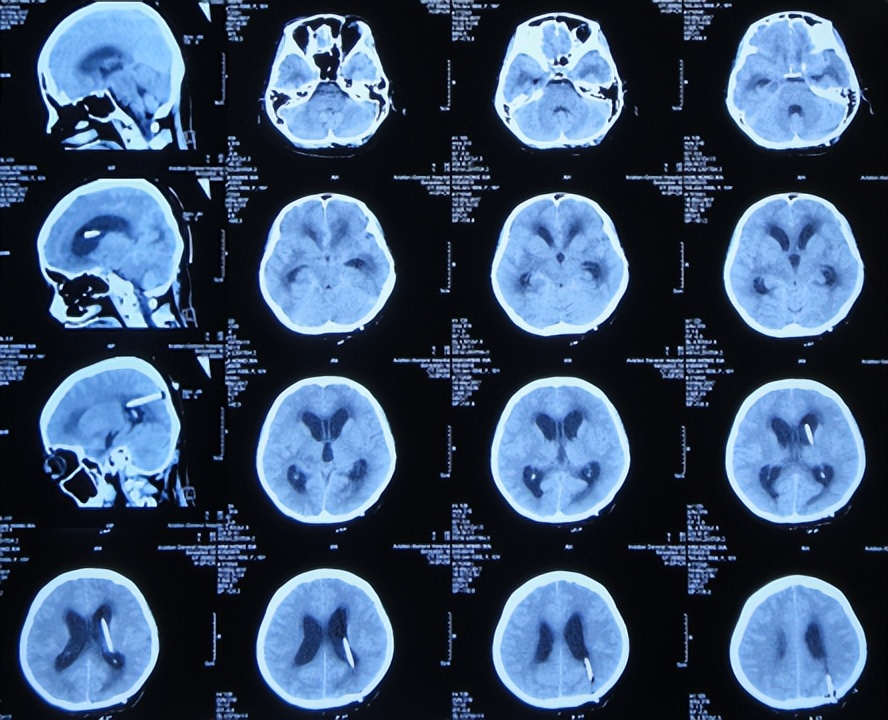

2017年4月2日(发病后13天),就诊于第2家的陕西省神木县某医院急诊外科,检查期间突发四肢软瘫、意识丧失、大小便*禁失**,查脑CT( 图-2 )后紧急收入ICU。

图-2: 2017年4月2日脑CT

行腰椎穿刺检查脑脊液常规:细胞高达1548×106 /L,淋巴细胞百分比56.8%,蛋白高达2266mg/l,糖1.15mmol/l,医院考虑结核性脑膜炎,家属当天晚上紧急将患者转至第3家的内蒙古的鄂尔多斯市某三甲医院。

入院时:意识不清加重12小时,头痛、呕吐、发热已10余天,给予经口气管内插管,呼吸机辅助呼吸;右眼外伤。腰椎穿刺检查测压大于330mmH2O,脑脊液化验:细胞总数1548×106 淋巴细胞百分比56.8%,蛋白1.6135g/l,糖1.65mmol/l。检查后考虑1、中枢性感染 化脓性脑膜炎?结核性脑膜炎?隐球菌性脑膜炎?。给予甘露醇降颅压,盐酸莫西沙星、美罗培南抗感染,给予异烟肼600mg/日,吡嗪酰胺0.5g/日,盐酸乙胺丁醇0.75g/日,利福平0.45g/日,甲泼尼龙琥珀酸钠40mg/bid,氟康唑0.4g/日,以及纠正酸中毒等治疗。